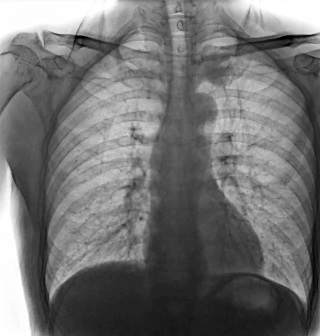

靜態(tài)DR受限于二維成像,在拍攝隱匿性病灶時,由于組織重疊病灶難辨,耗費(fèi)時間更長且易漏診、誤診。而動態(tài)DR則具備實(shí)時動態(tài)成像功能,可通過實(shí)時連續(xù)成像,對于重疊部位病灶或者易被遮擋的病灶進(jìn)行多角度動態(tài)觀察,快速實(shí)現(xiàn)動靜態(tài)轉(zhuǎn)換點(diǎn)片。

因此,動態(tài)DR在精準(zhǔn)診斷方面具有顯著優(yōu)勢。首先,有效減少誤診漏診,如胃腸道造影中,可實(shí)時觀察鋇劑的流動和充盈過程,精準(zhǔn)發(fā)現(xiàn)病灶部位,避免靜態(tài)DR攝片時機(jī)不當(dāng)?shù)膯栴}。其次,提升復(fù)雜檢查能力,如食管吞咽功能評估、四肢關(guān)節(jié)動態(tài)活動度評估等,動態(tài)DR都能提供關(guān)鍵性的診斷依據(jù)。同時,還可以優(yōu)化流程效率,醫(yī)生在擺位時能通過動態(tài)影像快速找到最佳投照角度,減少重復(fù)拍片,降低患者輻射劑量。